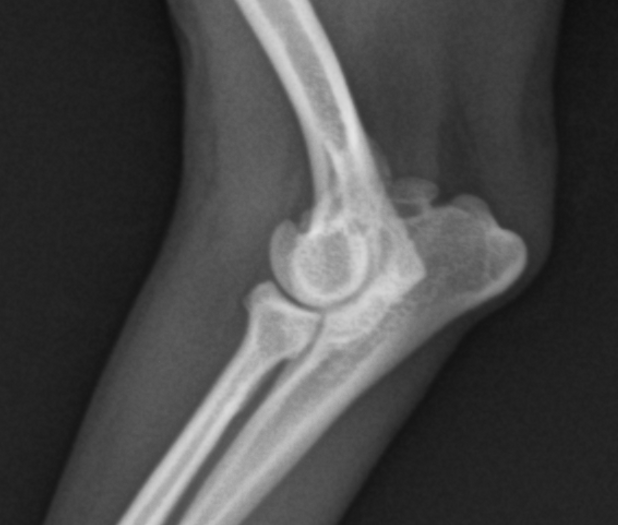

10yr CM miniature poodle UAP suspected case

ununited anchoneal process